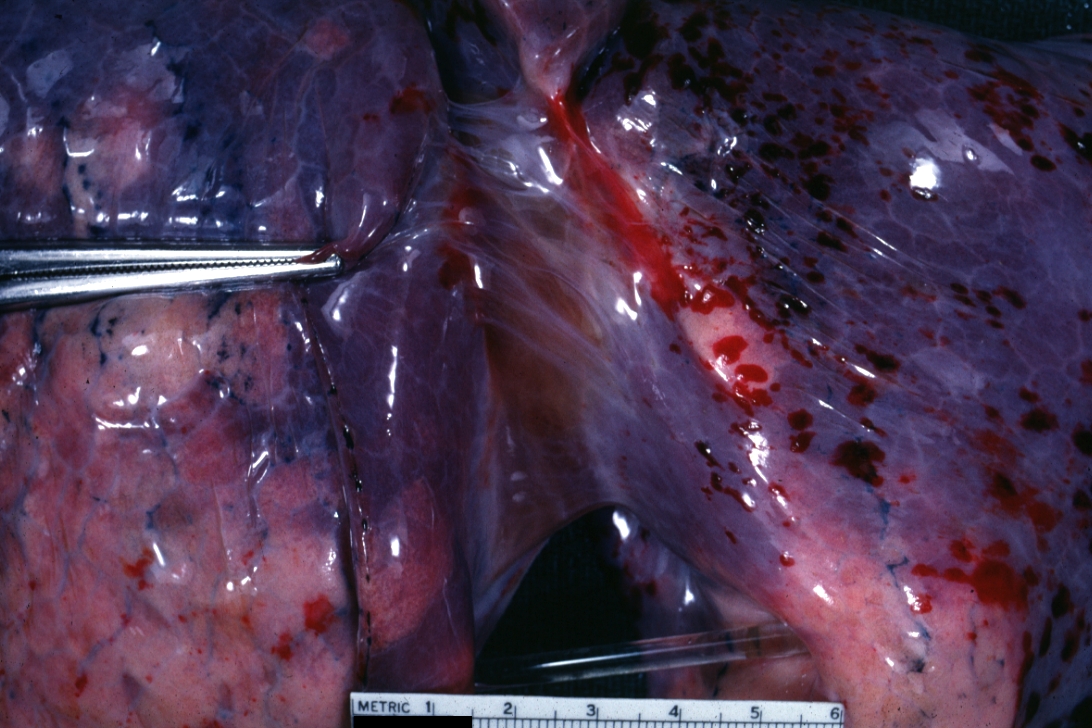

GROSS: RESPIRATORY: Lung: Amniotic Fluid Embolism: Gross natural color external view of lung showing a reddish blue color with focal subpleural hemorrhages